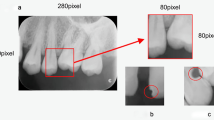

Dental caries is one of the most chronic diseases involving the majority of the population during their lifetime. Caries lesions are typically diagnosed by general dentists relying only on their visual inspection using dental x-rays. In many cases, dental caries is hard to identify in x-rays and can be misinterpreted as shadows due to the low image quality. In this research study, we propose an automatic diagnosis system to detect dental caries in Panoramic images, which benefits from various deep pretrained models through transfer learning to extract relevant features and uses a capsule network to draw prediction results. Using a dataset of 470 Panoramic images, our model achieved an accuracy of 86.05% on the test set. The obtained score demonstrates acceptable detection performance and an increase in caries detection speed, as long as the challenges of using Panoramic x-rays are taken into account. Among carious samples, our model acquired recall scores of 69.44% and 90.52% for mild and severe ones, confirming the fact that severe caries spots are more straightforward to detect and efficient mild caries detection needs a larger dataset. Considering the novelty of current study as using Panoramic images, following work is a step towards developing a fully automated system to assist domain experts.